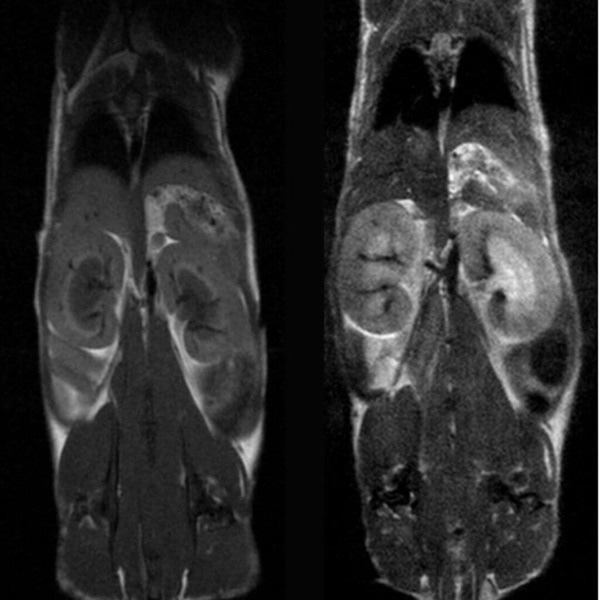

Anatomy & Morphology of mouse abdomen: T1- and T2- weighted scans of wildtype mouse body abdomen. Image Credit Scintica Instrumentation Inc

Tumor visualization in various cancer models: Fat-suppressed T2-weighted imaging can be used to detect and quantitatively characterize the growth of a wide range of cancer models. Image Credit: Scintica Instrumentation Inc

Hindlimb tumor growth: Monitoring the growth of xenograft tumor grown in the mouse hindlimb is identified with T2-weighted images. Segmentation of tumor region of interests (in red) on each tumor-containing slice allows accurate volume quantification. Image Credit: Scintica Instrumentation Inc

Cancer/oncology

The M-Series devices are suitable for studying various tumor types and disease phases. Since no alteration of tumor cells is necessary, models such as xenografts, orthotopic, transgenic, and patient-derived xenografts can be studied in a wide range of imaging subjects to focus on.

- Quantitative monitoring of tumor development

- Quantitative response evaluation for drug studies

- Tumor phenotyping, including necrosis detection

- Tumor detection

- Hypoxia and tumor hemodynamic microvasculature functional imaging (without contrast agents)

- Targeted molecular imaging with contrast agents

Fat-suppressed T2-weighted imaging can be used to detect and quantitatively characterize the growth of a wide range of cancer models. Image Credit: Scintica Instrumentation Inc

Monitoring the growth of xenograft tumor grown in the mouse hindlimb is identified with T2-weighted images. Segmentation of tumor region of interests (in red) on each tumor-containing slice allows accurate volume quantification. Image Credit: Scintica Instrumentation Inc